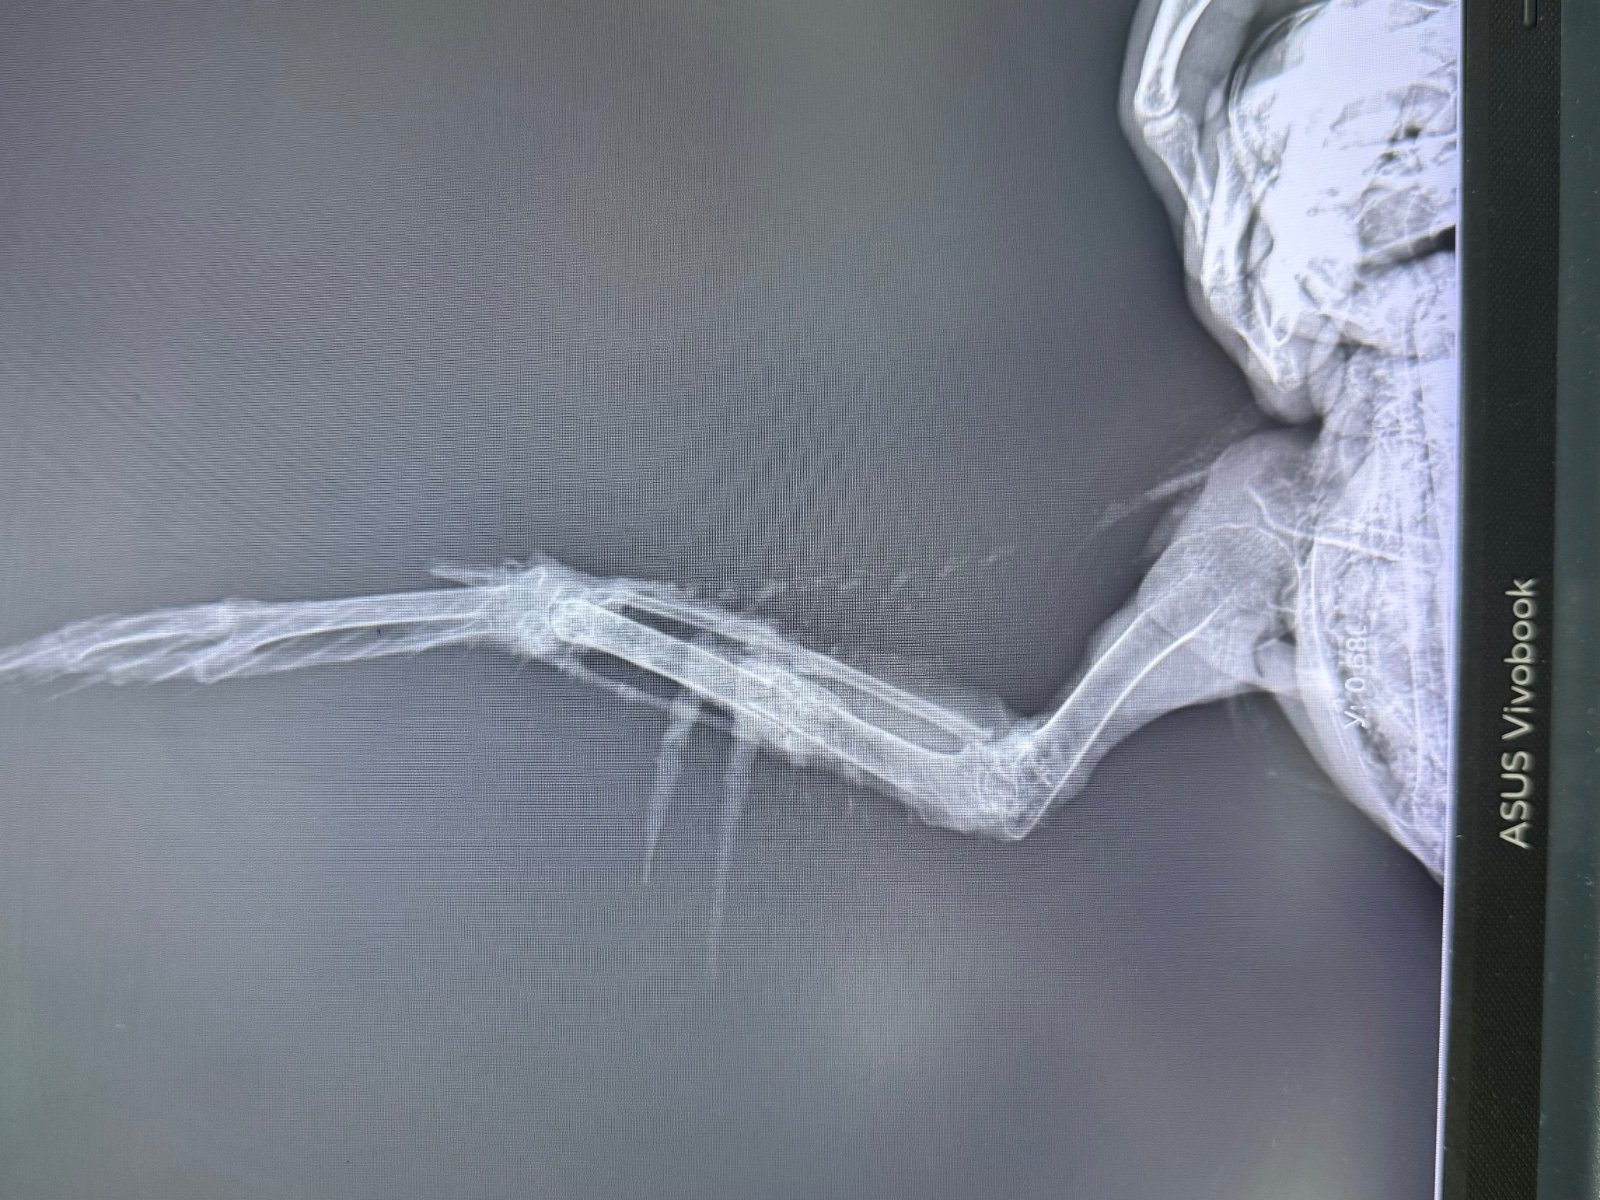

Здравствуйте! Подобрала молодого грача возле дома со сломанным крылом. В небольшом городе за лечение взялся лишь один ветеринар. Прооперировали 2 сентября опыта у меня нет, птицами никогда не интересовалась. После операции грачик хорошо питается (кормлю по гуглу - творог не жирный, мясо сырое, вареные куриные яйца; зофобас консервированный, гречка). Также даю минералы от зоомир общеукрепляющий. Активный, бесится, играется, танцует под гитару, но после операции меня немного побаивается, на руках больше не сидит как на первой фотографии. Сняли спицы 13 октября По поведению ничего не изменилось, кушает, пьет, бесится, по балкону до потолка взлетает. Но меня очень пугает, что крыло все еще висит и трясется. Последний рентген 23 октября Пожалуйста подскажите, что я могу сделать чтобы улучшить состояние крыла? Все ли хорошо по снимкам рентгена? Когда он начнет складывать крыло? Что я делаю не так? Из лечения никаких лекарств нам не назначали, только мумие. Я бы очень хотела оставить милашку у себя, но он уже бьется в окно, на улицу. Плюс мое место работы не позволяет заводить птиц, тк уезжаю на смену в другой город и не могу катать его с собой постоянно. Очень хотелось бы отпустить его к своим.